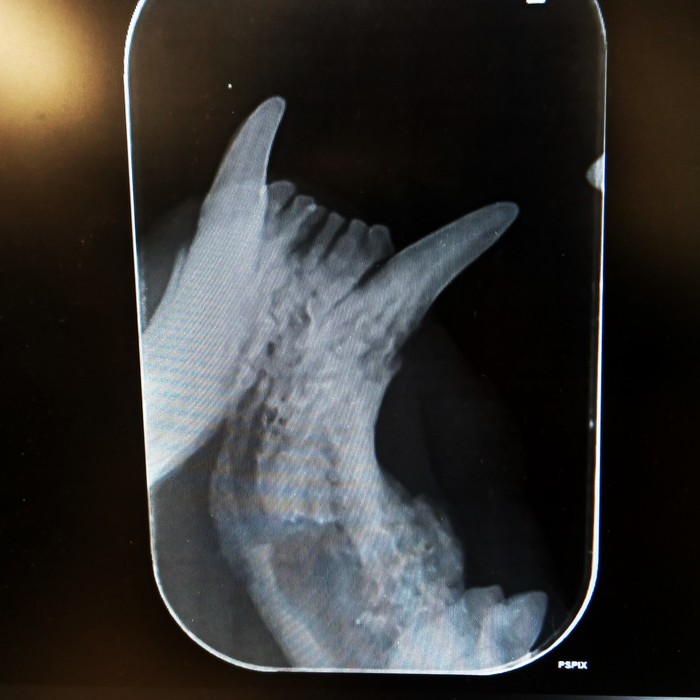

Rentgeny zubů se využívají na zobrazení hlubších vrstev zubů, kořenového systému zubů, posouzení parodontu a čelistních kostní.

Korunka zubu: přítomnost a celistvost skloviny, šířka dentinu a jeho případné patologie, šířka dřeňové dutiny, celistvost zubu, při frakturách rozsah zlomenin, hledáme resorptivní léze, kazy, částečné/úplné fraktury, změny tvaru a celistvosti korunky

Krček zubu: celistvost krčku, resorptivní léze, kazy, fraktury

Kořen zubu: posouzení cementu na povrchu zubů, dentinu, dřeňové dutiny, fraktur kořenů, tvaru kořenů a jeho případných výběžků, přítomnosti tzv. pulpálních kamenů, osteoresorptivních lézí

Čelist: posouzení případných periapikálních reakcí, přítomnosti, úbytku či změny struktury alveolární kosti, přítomnost zlomenin čelisti či nádorového procesu, ne/přítomnost některých zubů

kořenové anomálie

kořeny mléčných zubů

periapikální absces

polámané kořeny v čelisti

vstřebávající se kořen špičáku

resorptivní léze